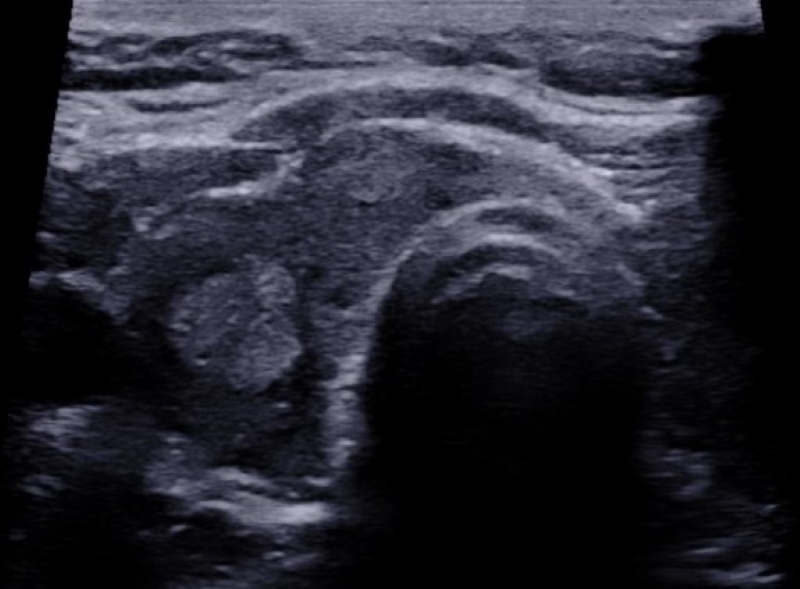

Ecogenicidad

Refiere al grado de ecogenicidad (no calcificado ni quístico) que presenta el nódulo respecto al parénquima tiroideo: hiperecoicos (Fig. 9), isoecoicos (Fig. 10) e hipoecoicos (Fig. 11). En el caso de los nódulos muy hipoecoicos (Fig. 12) se realiza la comparación con la ecogenicidad de los músculos adyacentes.

Si bien los nódulos malignos son más frecuentemente hipoecoicos, también lo son muchos nódulos histológicamente benignos20. Según la literatura los nódulos muy hipoecoicos presentan mayor riesgo de malignidad2,13,16, pero esta característica ha sido descripta solo en la población adulta.

En caso de nódulos con componente sólido y quístico la ecogenicidad debe describirse en relación con la porción sólida, con el fin de no confundir el término heterogéneo con el componente mixto sólido y quístico.

También podemos diferenciar los nódulos en homogéneos (Fig. 13) o heterogéneos (Fig. 14). Estos últimos contienen áreas con diferente ecogenicidad, y para poder brindar más información descriptiva es necesario mencionar el patrón predominante.